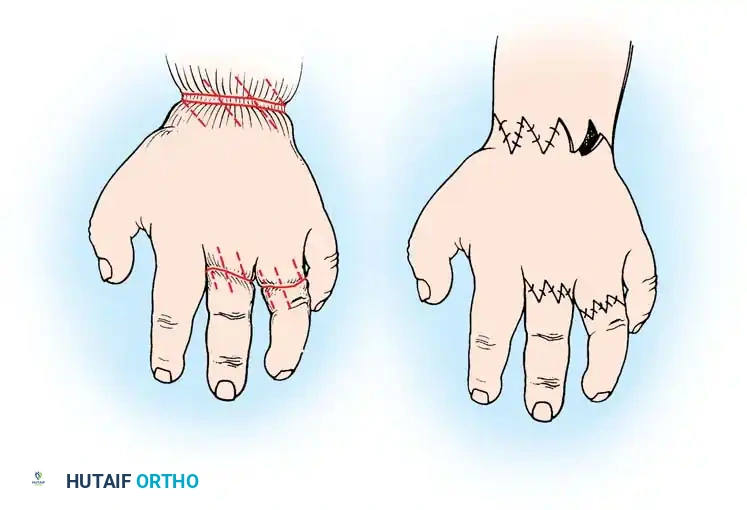

Surgical Planning and Marking:

- Examine the depth of the ring. Ascertain that you will only address one-half (180 degrees) of the circumference (e.g., the volar half or the dorsal half) during this initial procedure.

- Using a fine surgical marker, outline the multiple Z-plasty sites along the constricting ring. The central limb of each Z-plasty should lie directly within the deepest part of the groove.

- Design the triangular flaps with angles of approximately 60 degrees to maximize lengthening while preserving robust flap vascularity.

Management of Acrosyndactyly

Because the fingertips in acrosyndactyly are bound together by scar tissue rather than a failure of embryologic separation, the surgical approach differs slightly from simple syndactyly. The distal fusion mass must be carefully dissected to separate the terminal phalanges and nail beds.

* Thumb Reconstruction: A shortened, inadequate thumb severely limits hand function. Reconstruction may involve deepening of the first web space (using a four-flap Z-plasty or dorsal rotational flap) to increase the relative length of the thumb.